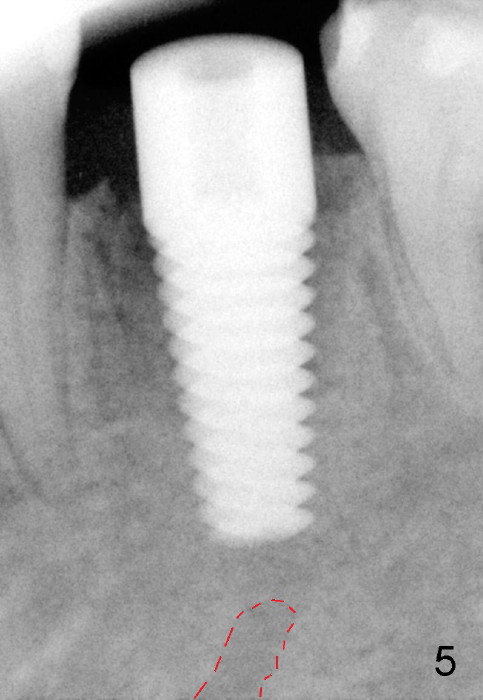

Taking multiple intraop X-ray is also necessary for depth adjustment (Fig.3-5).  For example, when a 5x20 mm tap is inserted at the depth of 17 mm, it is close to the mental loop (Fig.4), whereas the binding to the bone is minimal.  So a larger implant is to be placed at a shallower depth (Fig.5: 6x17 mm with insertion torque >60 Ncm).  The shallower implant placement creates limited space for future abutment and crown (Fig.6,7).  A short abutment will be used and the implant margin will be prepared as low as possible.  As expected, the wound heals in a week (Fig.8).